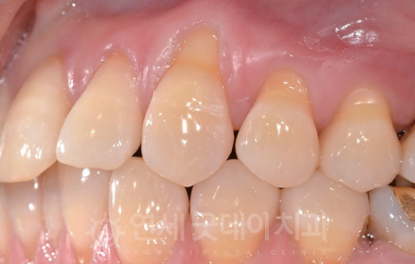

CASE 3 - 조직유도재생술

조직유도재생술 과정

마지막으로 살펴볼 것은 조직유도재생술 과정입니다.

사실, 많은 환자 분들이 잇몸이 흔들린다는 이유로

내원해 주시는데요. 이때 보면 잇몸과

잇몸뼈가 녹아있는 상태가 대부분입니다.

때문에 치아가 흔들리는 현상이 일어나게 되고,

이때 조직유도재생술을 고려하게 됩니다.

이는 잇몸병으로 인해 치조골이 불규하게

녹아내린 경우, 녹아내린 치조골 부위에 인공뼈나

자가골을 이식해 새로운 치주조직이 자라날 수 있도록

유도하는 치료법인데요. 잇몸이 자라서 들어가지

못하도록 차폐막을 사용하게 되며 치주판막수술이

동반될 수 있습니다.